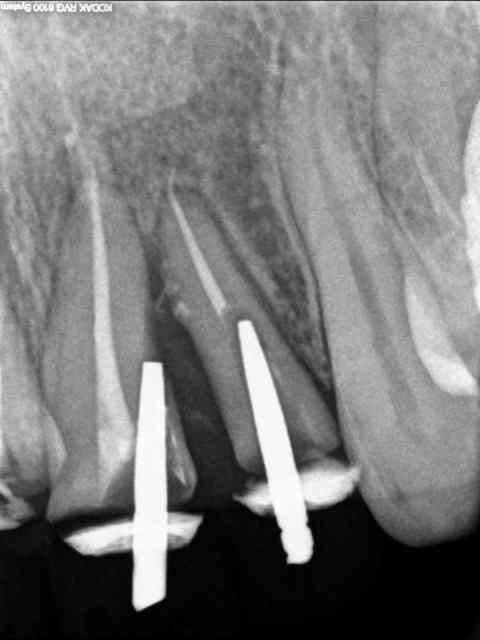

Et le gars ne se plaignait pas (ou comment implanter un pivot)